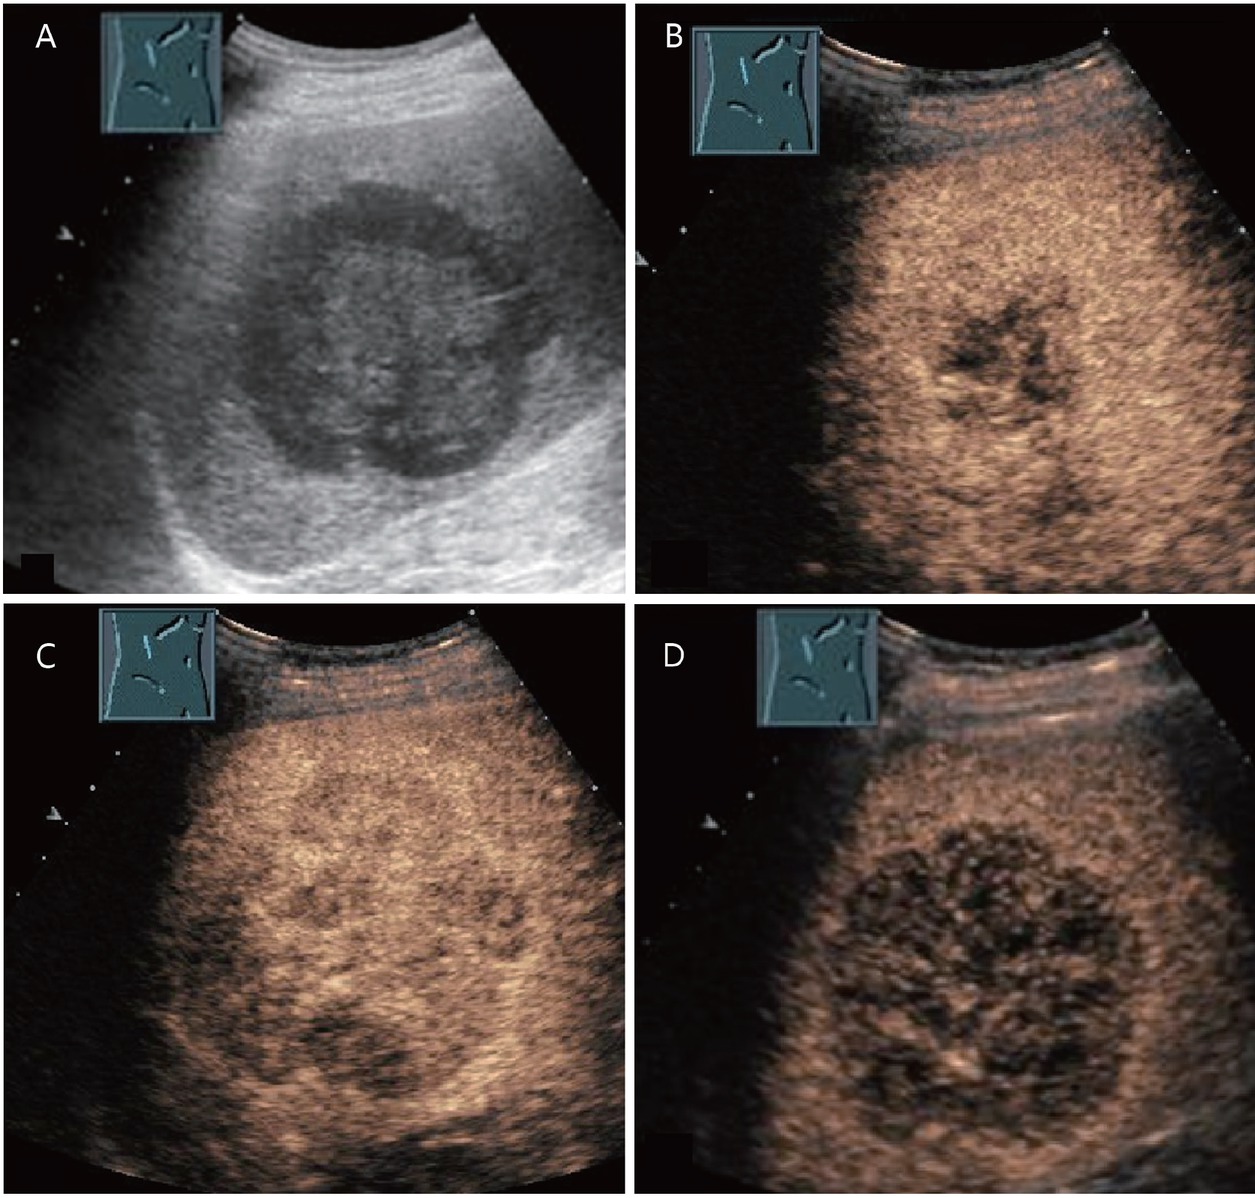

A typical feature of hemangiomas in CEUS is a smooth contrast-receiving ring in the arterial phase with a peripheral, discontinuous nodular (syn.: globular) enhancement with progressive centripetal contrast (Figure 1). The fill-in in the late phase can be complete or incomplete. (Partially) thrombosed hemangiomas do not fill up completely (Figure 2).[9,19]

A 65-year-old male with diabetes and past history of obesity. Hemangioma (in between markers) on the background of steatosis hepatis with severe fibrosis at shear wave elastography (9.5 kPa). Hypoechoic liver lesion in B-mode ultrasonography (A). On CEUS, smooth annular enhancement in the arterial phase (B). Smooth contrast medium lake in the marginal area in the portal venous phase (C). Complete centripetal filling in the late phase (D). Here typical hemangioma. CEUS provides the exact differential diagnostic assignment of a hypoechoic liver lesion in liver cirrhosis and makes further contrast-enhanced radiologic diagnostics unnecessary. CEUS: contrast-enhanced ultrasonography.